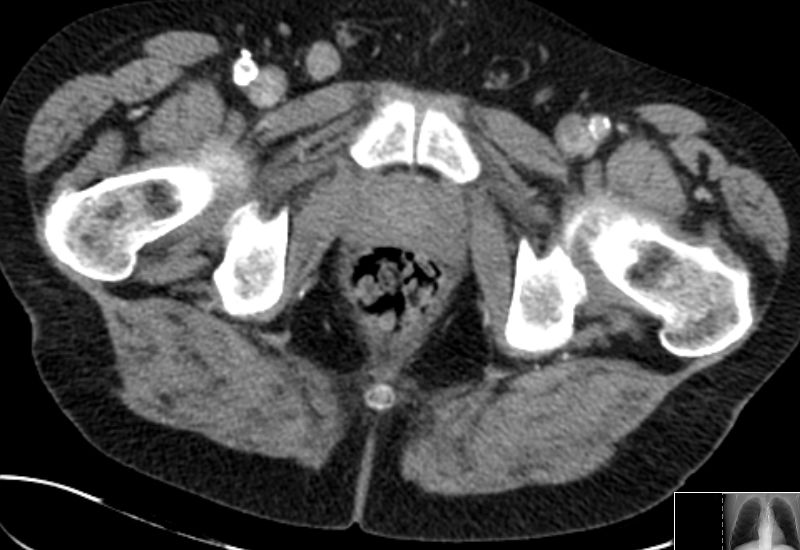

Zusätzlich ein 2,5 cm großen Lymphknoten in der rechten Leiste medial der Vena femoralis. ![]() |

![]() |

![]() | |

| Rektum | 70-jährige Frau mit Verdacht auf Rektumkarzinom. Histologische Plattenepithekarzinom.![]() | ||

![]() | ||